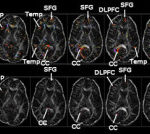

The following illustrations are from a case involving a 9-year-old boy who suffered a “so-called” mild traumatic brain injury in a car accident. Of course, when you look at the damage to his brain, one would seriously question the label “mild.”

We use our expertise to review symptoms that are often associated with brain injury, and we follow our clients as they “heal” to determine if the client, family members, or friends observe any changes in cognitive, physical, emotional, behavioral or sleep functioning. We use checklists to cover such items as reduced attention and concentration, memory problems, problems making decisions, depression, impaired judgment, dizziness/balance problems, blurred vision, ringing in ears (also known as tinnitus), alteration of the sense of taste, and/or smell, and many other indications. Often, these forms of deficits are only documented and recognized as a result of a specialized evaluation done by a neuropsychologist, an audiologist, a sleep specialist, or an otolaryngologist (ENT). In other cases, documentation of subtle forms of brain damage may be identified with specialized imaging techniques known as PET scans, SPECT scans, functional MRI evaluations (fMRI), or the latest technology available (including the use of a high-field MRI magnet, known as a 3.0 Tesla, together with Diffusion Tensor Imaging and volumetric assessment).

It is not the purpose of this summary to provide an exhaustive summary of the software options available for analyzing brain structures. However, two of the most useful computer sequences for assessing the structural integrity of the very small components of the brain are 1) Diffusion Tensor Imaging (“DTI”) that assesses the integrity of the brain’s white matter fibers; and 2) Volumetric Analysis that examines the brain volume for specific structures or brain segments.